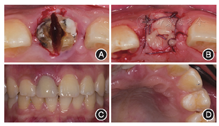

选择不翻瓣颊舌向分根拔除患牙,保护唇侧骨板[2]。

鉴于11根尖区骨质破坏范围较大,无法提供即刻种植所需的初期稳定性,故拔除残根后行位点保存。彻底清理牙槽窝,生理盐水和双氧水反复冲洗,拔牙窝内放置足量骨替代材料(Bio-Oss骨粉,Geistlich,Wolhusen,瑞士),取上颌左侧前磨牙腭侧角化上皮腭黏膜半厚瓣,覆盖并关闭拔牙创口,纤维带粘接桥临时修复11(图3)。

像;D:腭侧术区2周后复查愈合良好